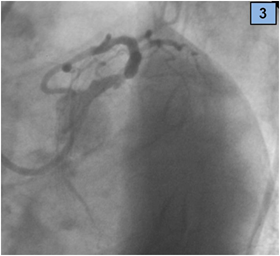

We present a 45-year-old man that was admitted to an emergency department with a history of sudden-onset, severe central chest pain associated with nausea and dyspnoea. Regarding cardiovascular risk factors, he was an active smoker (20 daily cigarettes) and had dyslipidaemia. On hospital arrival, he was lucid and oriented, had normal heart sounds and fine right basal inspiratory lung rales; arterial blood pressure was 120/70 mm Hg and heart rate 76 beats/min. The electrocardiogram showed sinus rhythm with ST segment elevation (4 mm in leads I and aVL, 2 mm in lead aVR), so emergent coronary angiography was indicated. The coronary angiogram showed an image suggestive of rupture plaque, that was located in the distal segment of the LMCA (Figure 1). There were also other lesions, a thrombotic total occlusion of the proximal circumflex (CX) artery and a severe stenosis of the proximal left anterior descending (LAD) artery (Figures 2 & 3). Right coronary artery was dominant with no lesions.

Figure 3 Severe distal LM and ostial LAD lesions with thrombotic occlusion of CX artery, LAO 50 Caudal 30 view.